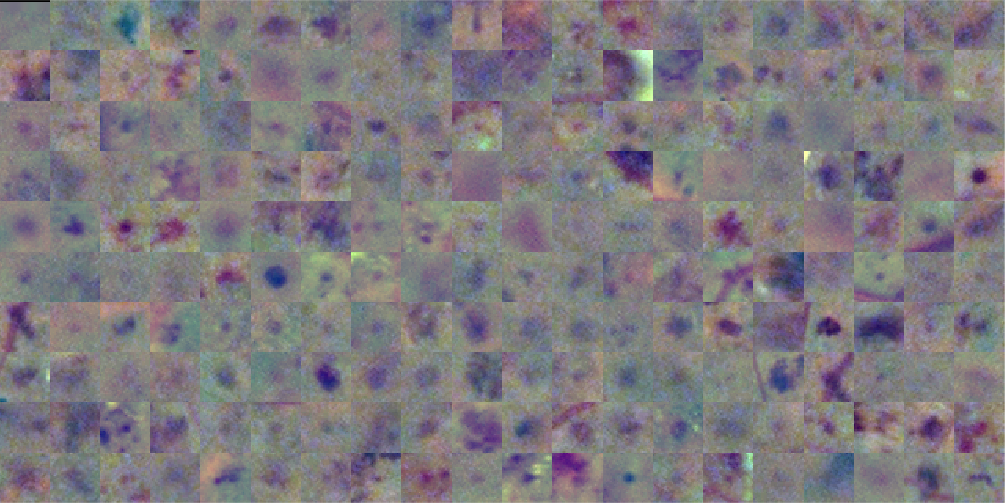

Figure 5 presents a random sample of the potential lesions retrieved by the method on a randomly selected image from DIARETDB1 training set. It is possible to see that most of false positive samples correspond to vascular branching or crossing points, vessel segments and beadings, scars due to laser photocoagulation or black spots of dirt in the capture device, as reported by Seoud et al. (2016). This setting underlines the importance of refine the candidates to remove false positives.

A training set is built for training the CNN, where each sample is a square patch around the center of each red lesion candidate, as extracted from (Figure 5). The patch size is taken as double the length of the major axis of the candidate, or pixels if the major axis of the candidate is smaller than 32 pixels. This setting let us to recover not only the candidate itself but also its surrounding area, which allows the CNN to capture both candidates’ internal features and information about its shape, borders and context. Patches larger than pixels are downsized to this resolution to ensure a uniform input size for the CNN. As windows are square by definition, this transformation is isotropic and does not affect the appearance of the lesion candidate. Samples are centered by subtracting the training set mean image. Alternative scaling methods such as ZCA whitening and contrast normalization were also analyzed, although no improvements were observed on the validation set when applying them. The label associated to the candidate is assigned according to the ground truth labeling on the data set: if the candidate overlaps with a true labeled region, then the window is assumed to be a true red lesion (); if it does not, then it is assumed to be a false positive (). The CNN is trained from scratch on an augmented version of this training set, which is obtained by rotating each patch by or , and then flipping the resulting windows horizontally or not. Thus, for each input patch, 8 new patches are generated.

In order to assess the visual appearance of the deep learned features, a graphical representation of the 32 filters of size learned on the first layer of the CNN is presented in Figure 13. These representations allow to verify which types of high level characteristics are detected by the first layer of the network (Zeiler and Fergus, 2014). Thus, they are suitable to confirm if the network was trained for long enough, as well-trained CNNs usually display smooth filters without noisy patterns, as in this case. From Figure 13(a) it is possible to see that filters learned in Experiment 1 are mostly descriptors of the color properties of the lesions. This setting is in line with the fact that the training set used in this case contains not only small MAs but also medium size HEs, which can be more easily described in terms of their internal color homogeneity rather than their edges, which significantly varies from one to another. Other filters are able to capture purple, ellipsoidal structures corresponding to true lesions like those illustrated in Figure 5(b). This last type of filter is more common in the first layer of the CNN learned in Experiment 2 (Figure 13(b), which might be associated with the smaller true positive structures observed in the training set built with ROC and DIARETDB1 MAs.